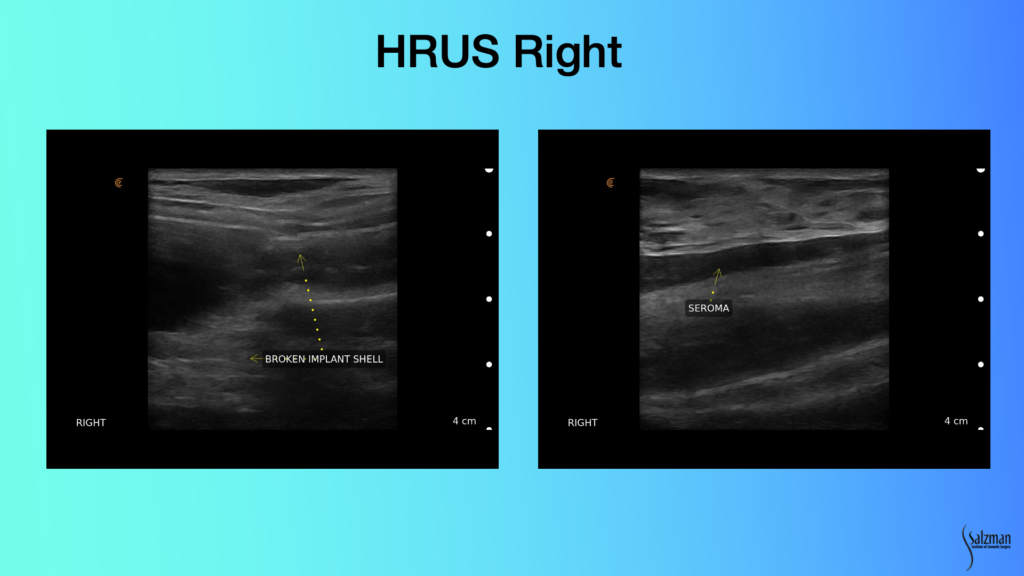

Looking at this implant with ultrasound, you don’t have to be a rocket scientist to know that this image on the left does not look like what I just showed you as a normal implant. The railroad tracks are not straight anymore. There’s a bend right and it’s disheveled looking. And there’s stuff that looks like a snow, which is free gel. It’s called a snowstorm pattern of free gel. And you see little fragments of gel of the elastomeric shell that are embedded inside the material, which should be on the inside of the implant.

And then we see this hypoechoic area which is fluid. Fluid is black, or hypoechoic. It doesn’t produce many echoes from the ultrasound. The right side is broken and has a seroma. This is clearly a textured implant because it doesn’t have that smooth appearance that we saw in the previous slide. With a seroma on eight-plus-year-old silicone gel implants that are textured, we’ve got to start worrying about ALCL.

If you look at the scale of this seroma, it’s less than a centimeter. It’s going to be hard to put a needle in this. In Louisville, you need 10 cc of fluid to get cytology sent. There’s no way I’m going to get 10 cc out of this lady, so I’m not even going to try and aspirate. Because it’s already a broken implant, and it’s eight-plus years old, we’re going to the operating room, which obviates the need to send her for an MRI that’s confirmatory.

First of all, I’m 100% sure I’m right. I know it’s broken. I don’t need an MRI. And I don’t need to send her to a radiologist for another $1,000 to tell me that he can’t aspirate it. And if he does, he’ll only get 3 cc. It would be a waste of time. So, I scheduled her for surgery, which she’s much happier with.